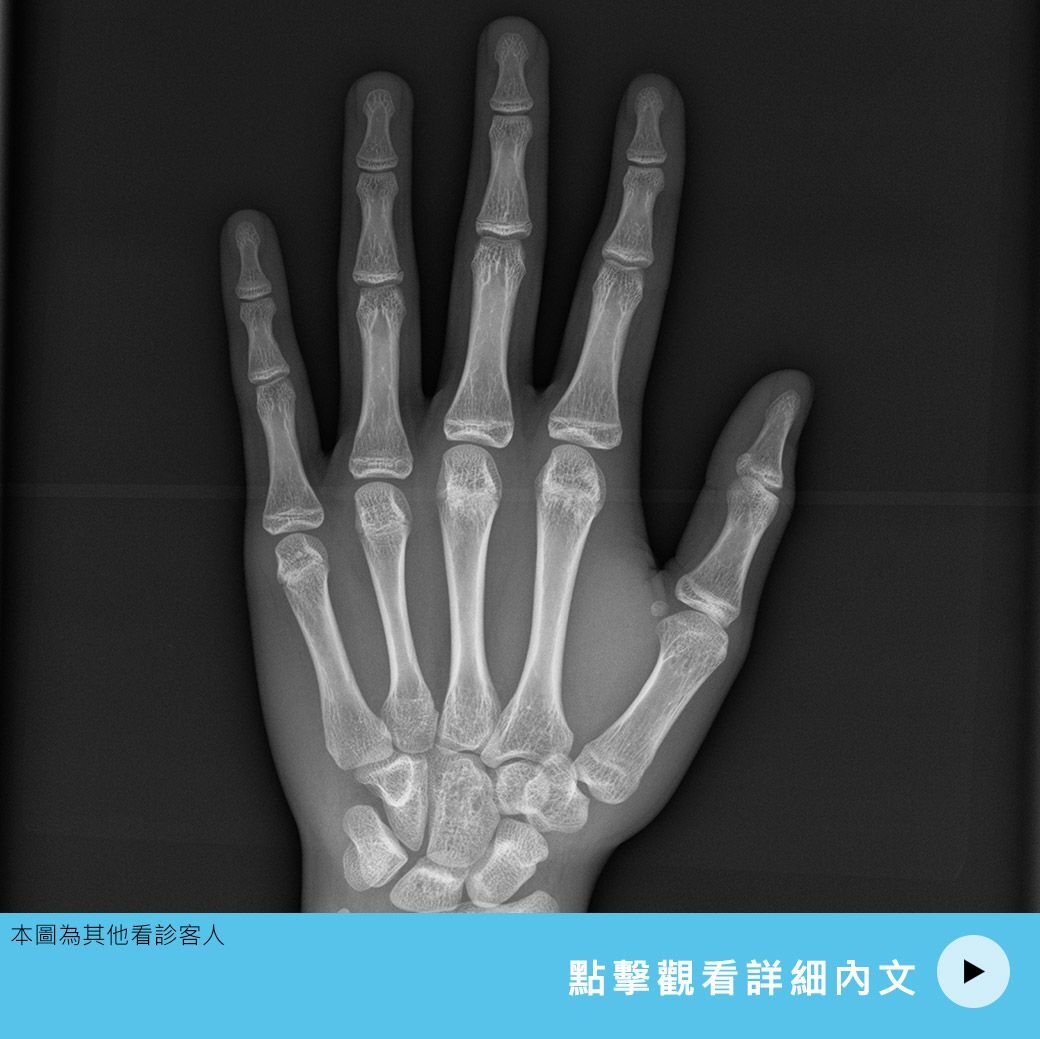

我們來看手腕和手掌的X光 每根手指頭(指骨) 還有我們的掌骨還有尺骨、橈骨本身也都有生長板 那包括中間的腕骨 小孩子的時候是一種軟骨 等到越接近成熟的時候它變成骨化就會越來越像大人腕骨的一個形態 在不同的年紀 每個指骨、腕骨它生長板閉合的時...

只要是長骨的部分 我們兩端都會有一個生長板 隨著年紀的生長 生長板它也會慢慢的變成熟 到青春期的時候 生長板會從軟骨變成骨頭 腕骨化 那這個時候就定型了 那骨齡是過去50年前歐美的一個學者 他們去收集不同年紀的小孩子手掌的X光 去看手指的指...

為什麼要測骨齡 臨床上父母常常會在意小孩子 身高比較矮小 我們並不知道小孩子實際上 他骨頭成熟的一個狀況 我們是可以去照手掌的X光 可以去判斷小孩子的骨齡跟他實際的年齡的一個關係 我們透過骨齡的檢查 才可以預測小孩子未來還有多少的潛能 我們...

過去照了骨齡的一個X光的檢測的話 我們是需要去對骨齡的圖譜 這個圖譜裡面總共有一百多張X光 它其實分別記錄 青少年時期不同年紀的一個 骨齡生長板閉合的狀況 因為要對一百多張的X光 所以過去傳統是用人工去比對 通常耗時要幾個小時 甚至到一、兩...

X光看骨齡是看骨頭裡面的生長板粗細 剩下多少的厚度 然後再看骨頭的形狀 這樣子的閱讀方式 其實我們以人工閱片 我們判讀骨齡的方法目前在全世界有兩種方法 如果是醫師 不管是放射科醫師 或者是小兒科醫師、或者是骨科醫師 他們在閱讀的時候 我們用...

骨齡追蹤是根據科學的方法 照X光然後看骨頭裡面的生長板,估計還剩下多少 然後我們來預估這樣的生長板還可以給小朋友多少的公分數 那當然就是當下只能看到現在的骨齡 然後預估現在有可能會給他多少的身高 但是骨頭的年齡是會隨著時間改變 而且不見得會...